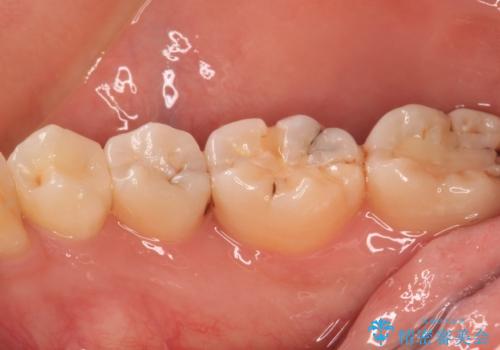

- 奥歯に頻繁に物が挟まるとのことで来院された患者様です。

最近ものが挟まりやすくなったり、冷たいものがしみるようになったりといった症状があり、診査したところ、むし歯や歯質の欠損、不適修復物などが認められました。

精度の高いセラミックインレーによる修復治療を行うこととしました。

処置を行った歯以外にもむし歯と思われる歯が多数ありますが、費用のかかる治療であれば、優先順位をつけて、処置を急ぐ歯から処置を進めて行きました。